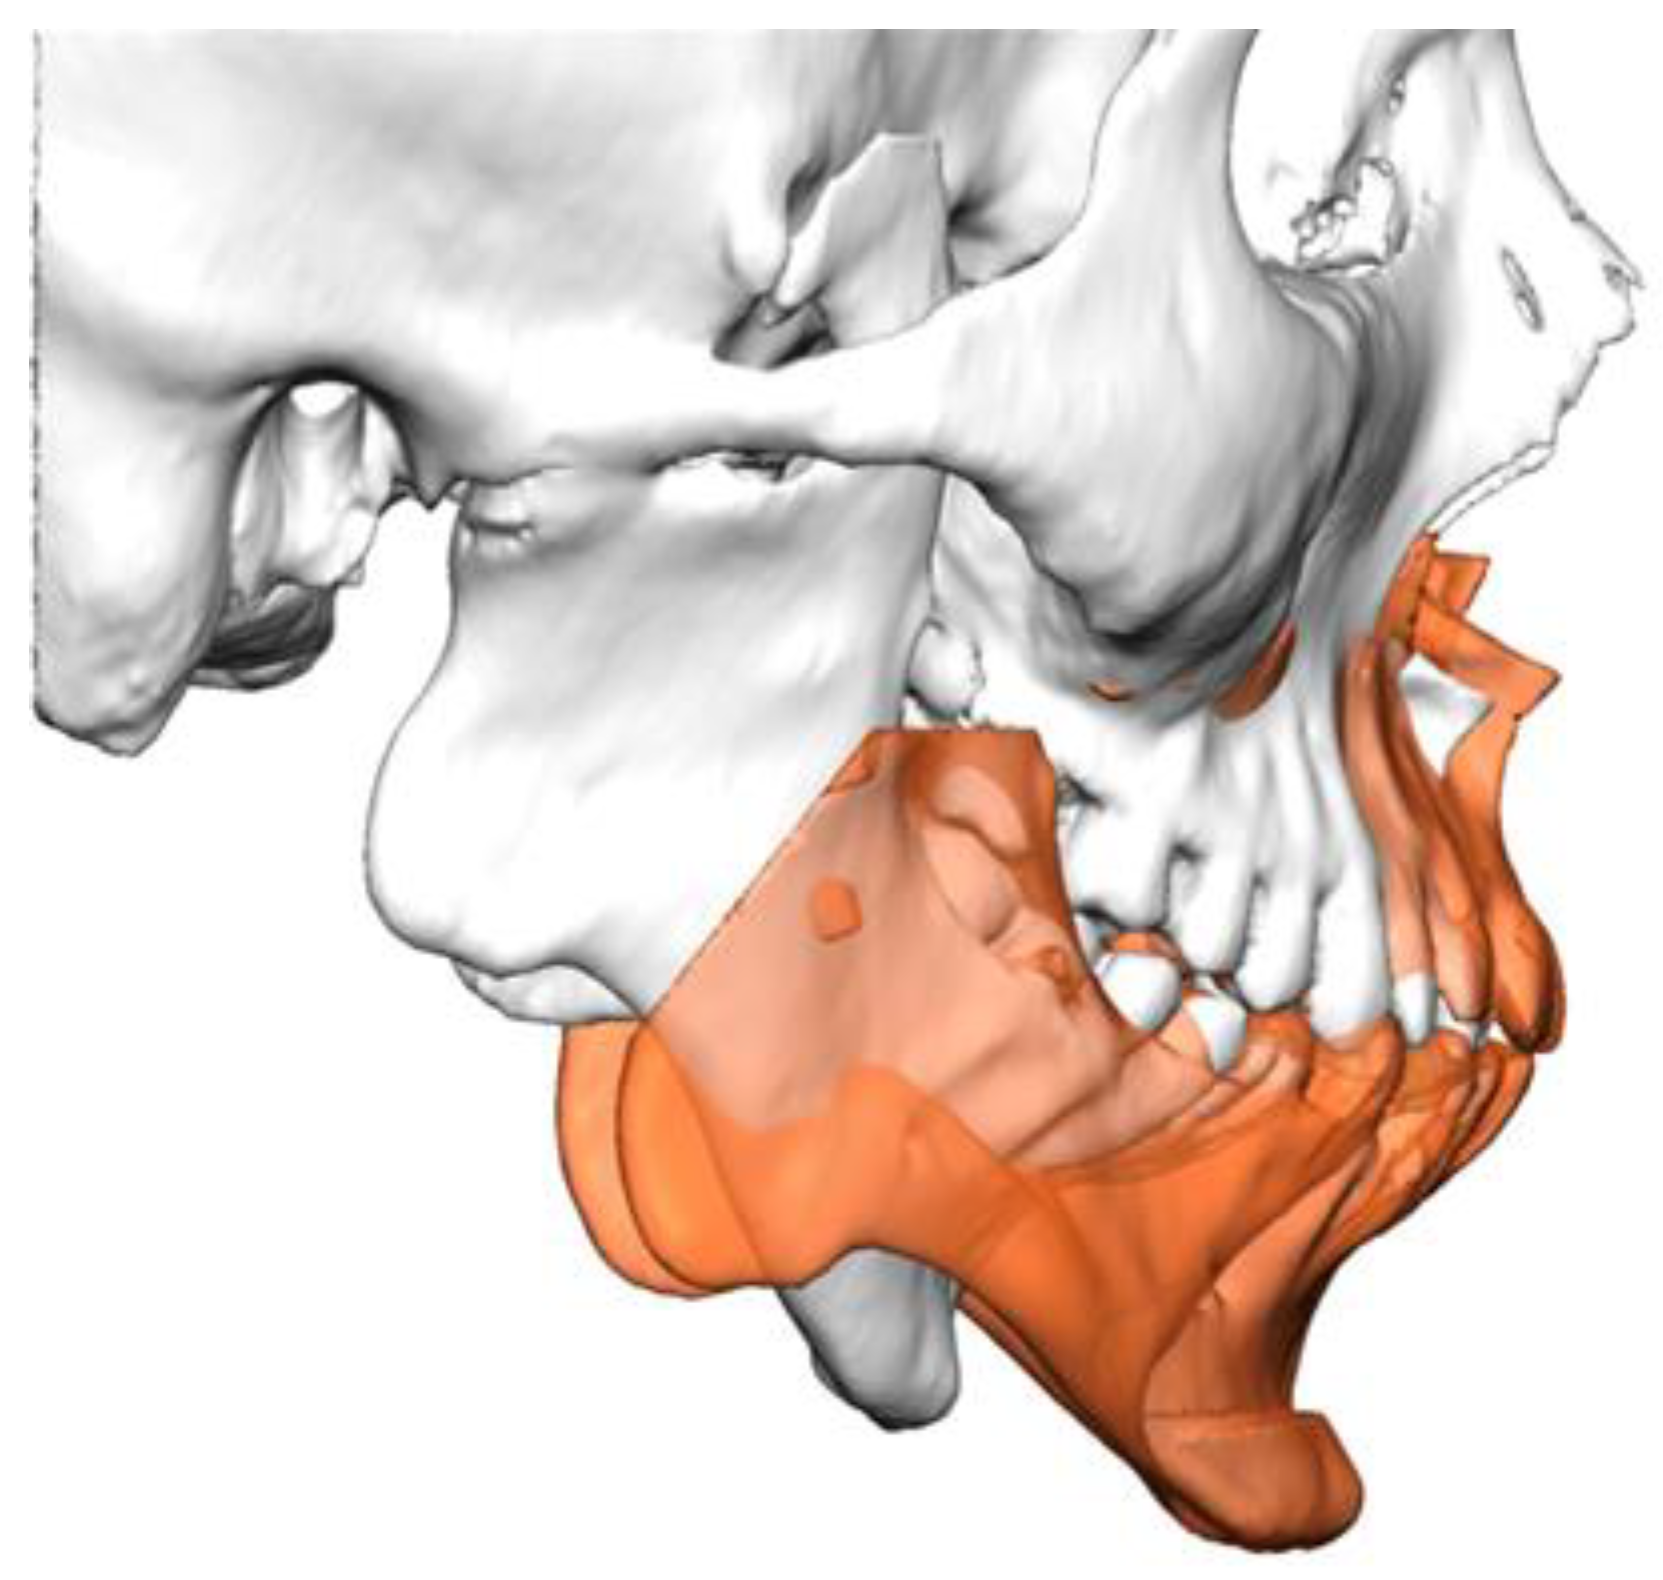

2.2. Virtual Surgical Planning and Computer-Aided Manufacturing Workflow

2.3. Surgical Technique

2.3.1. Mandible